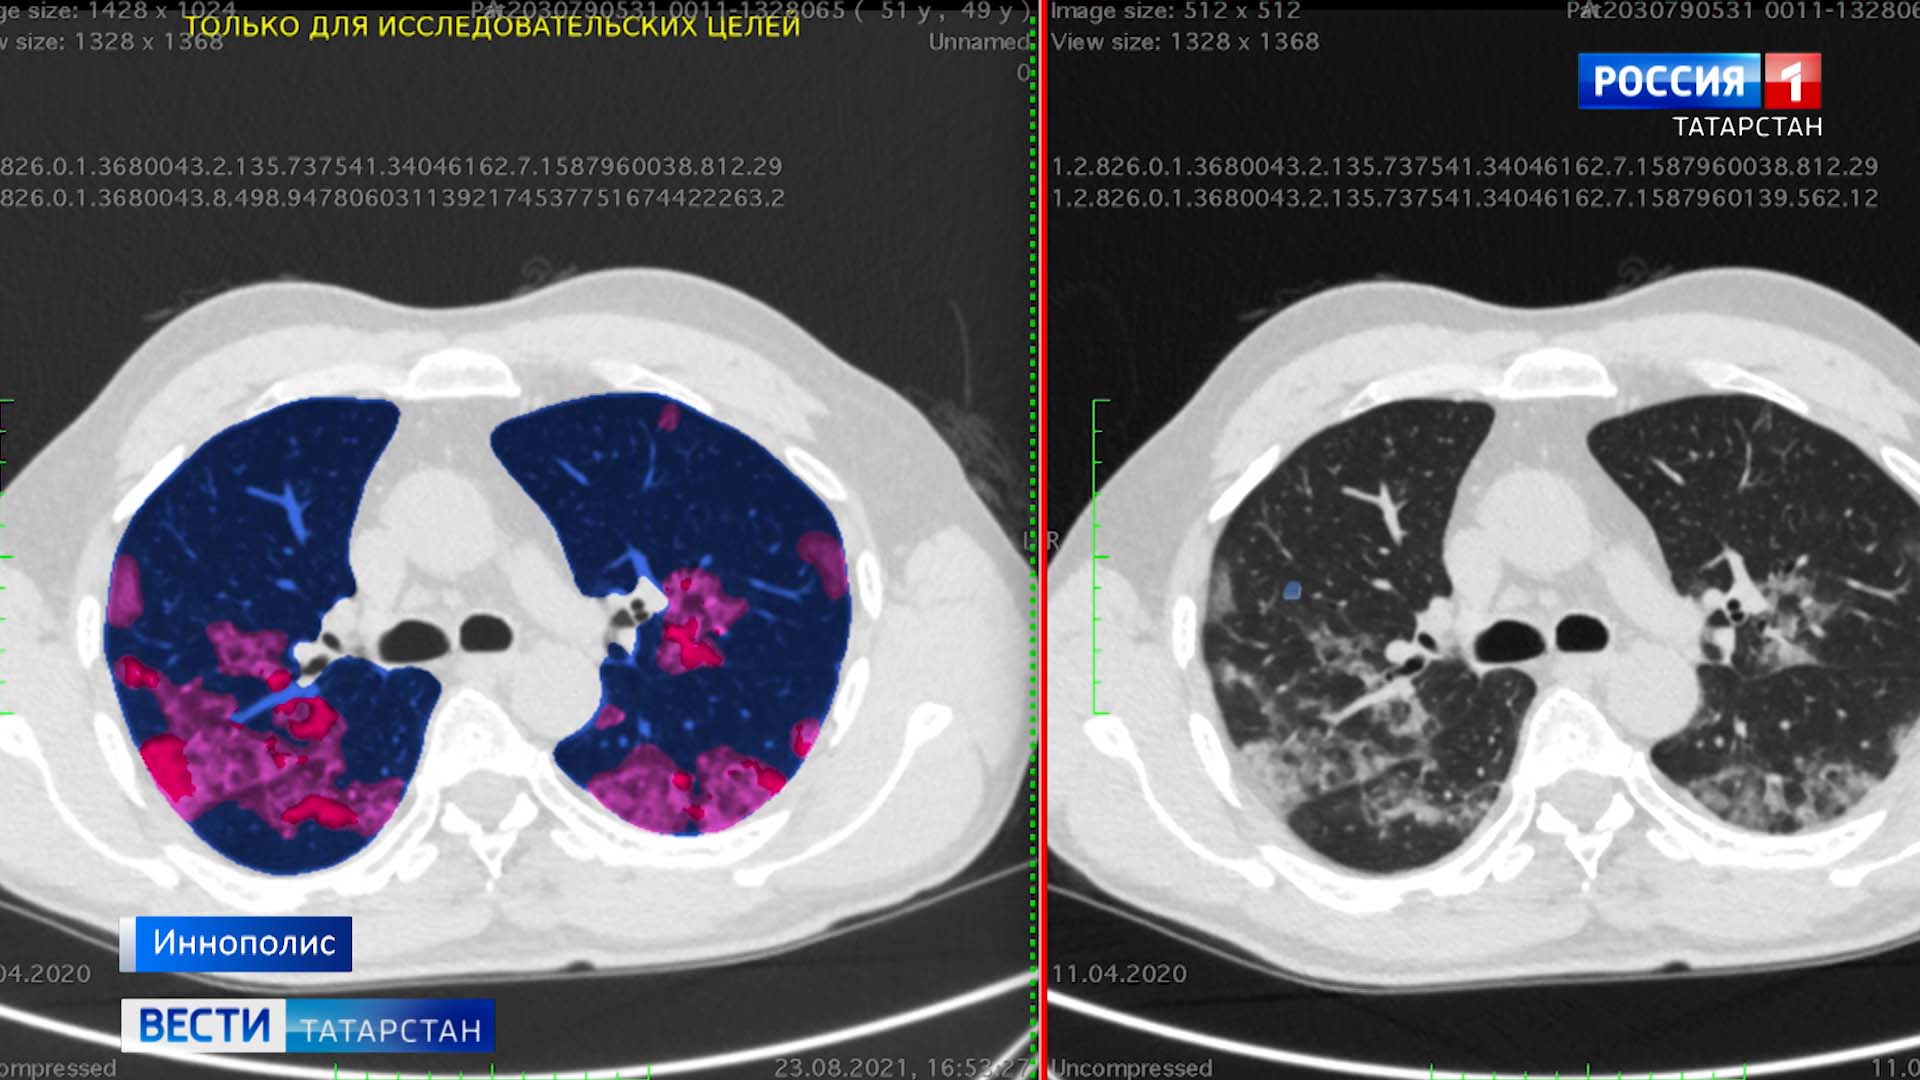

В привычную работу врача они действительно вносят новые краски. Вот еще одна разработка — в черно-белые рентгеновские снимки вглядывается нейросеть и выделяет пораженные области цветом.

Мария Шаблинская, руководитель регионального офиса

— Вы видите рабочий стол рентгенолога. Где цветные области означают те или иные патологические изменения. Это помогает быстрее делать диагностические действия, точнее, если вдруг квалификация недостаточна